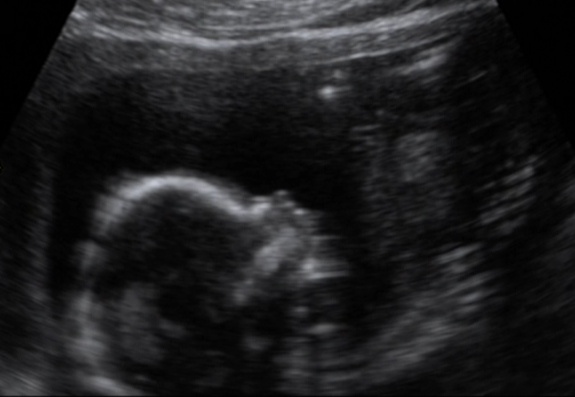

ג' היה בטוח שזו בת- בכל מאודו

ואני הייתי בטוחה שזה בן.

כל כך הופתעתי ביום שלישי, בסריקת המערכות.

המעברים האלו בין אולטראסאונד אחד לשני בחודשים הראשונים

זה סיוט מתמשך וכואב.

לא מרגישים את העובר כל כך וזה מלחיץ.

רציתי לדעת שהיא חיה.

אנחנו שנינו מאוהבים בה וזה מטורף  - להתאהב במישהי שאתה לא מכיר

כל כך חזק .

היא מתוקה, השתוללה בזמן הבדיקה ובכל פעם שניסינו למדוד משהו

הפנתה לנו את הגב והישבן.

אני מקווה שזו נבואה לכך שהיא לא תיכנע למרות.. גם לא לזו שלי.

לפי צילום תלת הממד יש לה את האף של ג' – בוודאות.

מזל שלא את האף של המשפחה שלי.

עכשיו חייבים להירגע עד לפגישה הבאה שלנו איתה.

אבל אני חושבת שאני כבר מרגישה אותה.

לא בטוח – אולי זה גזים.

שבוע 17.